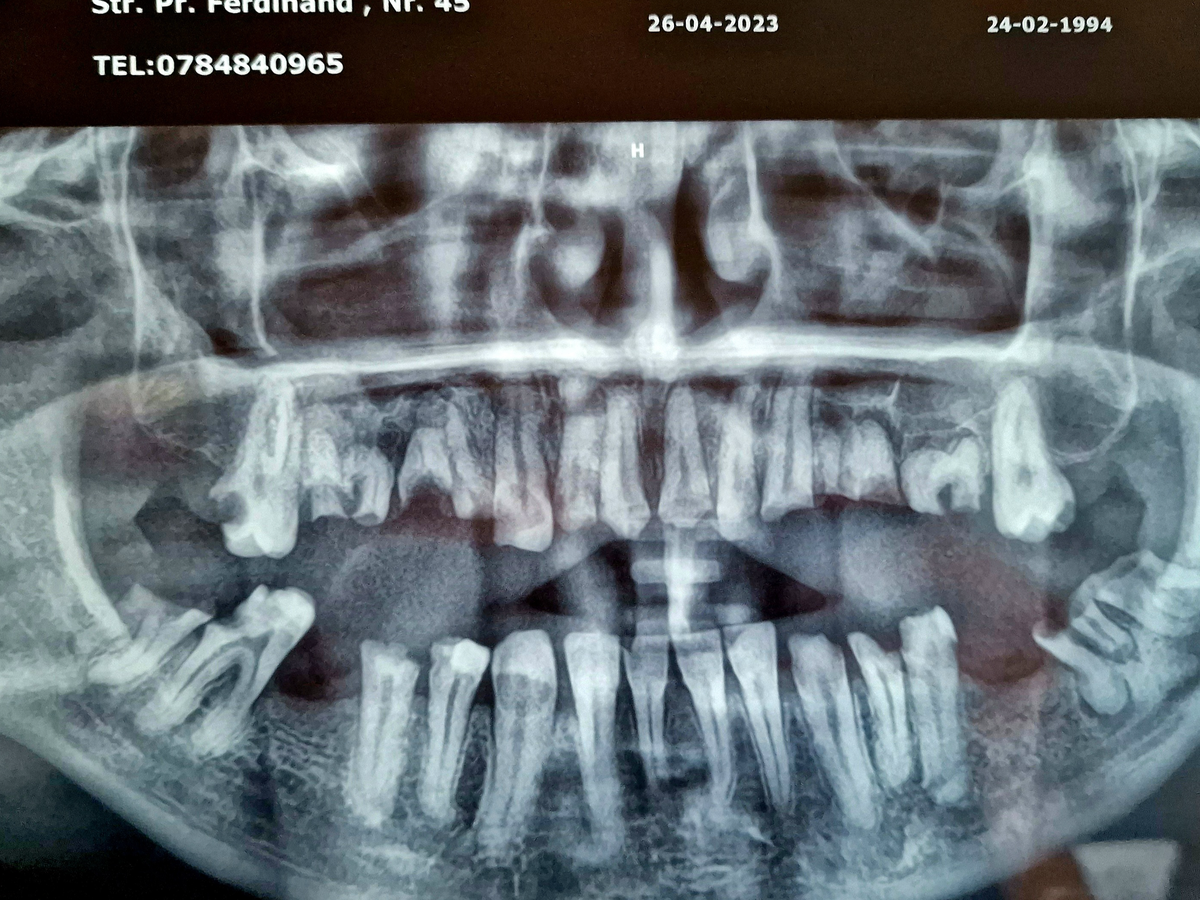

Hello, my name is Cătălin, I'm 31 years old, and I'm from Romania. I'm asking for your help with a problem I've had since childhood, which has started to affect me more and more as the years go by. It’s about a dental problem, and after several check-ups, it was concluded that it’s a hereditary disease, periodontosis, which my father also has. Although I've strictly followed oral hygiene since I was young, I noticed that my teeth and molars began to decay from the root. The cavities advanced to the point where, while eating, pieces of my teeth or molars would break off, even from something as soft as bread. When a molar broke or a tooth became decayed, I would go to the dentist, where they would fill the cavity and send me home. However, over time, I noticed that my entire dentition started to deteriorate from the root, and occasionally, I would find that a molar or tooth would break off at the base of the gum. Regardless of what I ate, I avoided hard foods and was very careful with my diet, knowing that my teeth were very fragile.

Three years ago, four of my upper teeth broke, leaving me with only one. I improvised a plastic mouldable denture (found on Amazon) with which I can still speak, although not very clearly, and I can still smile, albeit with some embarrassment, being the target of jokes from people who don’t understand that anyone can end up in such a situation. In my lower jaw, I have five teeth and only one molar left, which barely helps me to eat. The rest of my teeth are destroyed, with the teeth and molars broken at the base. Last year, in a moment of vulnerability, I inquired with several clinics about the cost of restoring my teeth, both in Romania and in Turkey, where I heard it is cheaper and faster. The cheapest option I received was from a clinic in Turkey, based on a 3D scan of my teeth. In total, the cost would be £13,000, including 12 implants, 2 bone grafts, and the temporary denture, with the permanent denture to be fitted later. They informed me that I need 6 implants on the upper jaw and 6 on the lower jaw because, due to the disease I suffer from, fewer than 6 implants per arch wouldn’t provide enough strength, as the bone is quite weak.